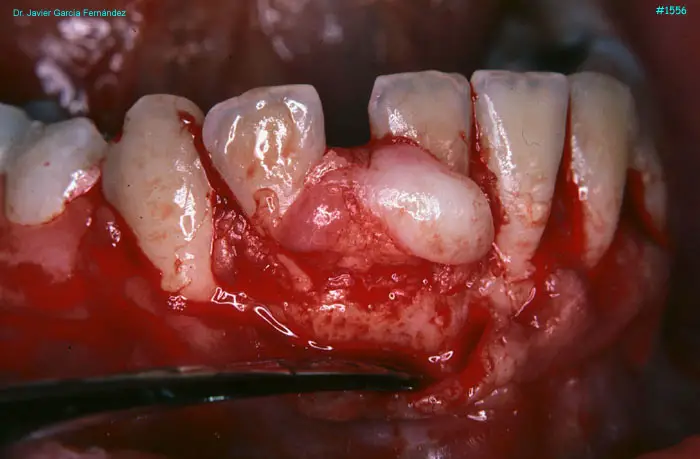

Atlas of Surgical Techniques in Periodontics. Chapter IV. Atlas de Técnicas Quirúrgica en Periodoncia

image 082